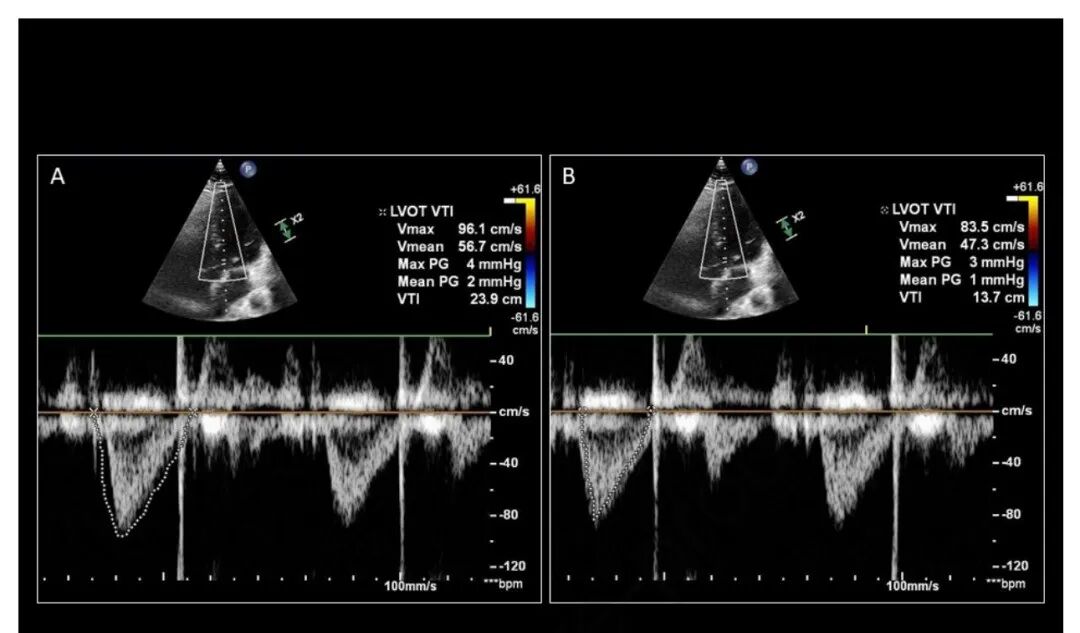

准确获取 LVOT VTI 跟踪非常重要。这要求 PW 多普勒采样线与 LVOT 内的血流平行。如果声波角度在 20° 以内,实际多普勒频移误差 ≤ 6%,导出的 SV 将是可靠的(图 4)。PW 采样点也需要放置在主动脉瓣近端,而不是 LV 腔本身内(图 5)。获得良好的 LVOT VTI 由内部“暗”和明亮“轮廓”的光谱包络表示。追踪 LVOT VTI 时,尽可能精确并尽可能接近外边缘非常重要(图 6)

图 6. 显示从相同 LVOT VTI 的过度跟踪 (A; 23.9cm) 和跟踪不足 (B; 13.7cm) 获得的值的显著差异。